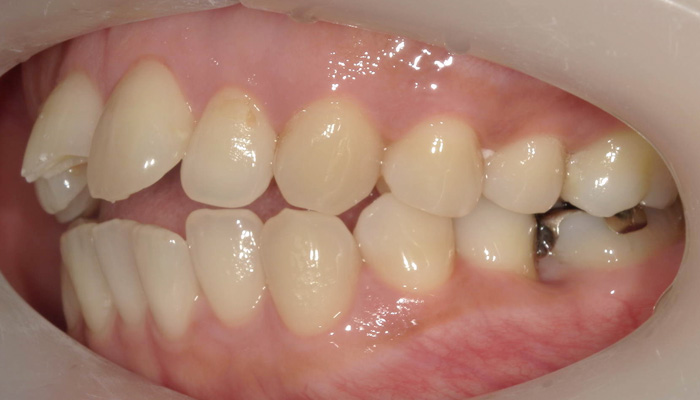

初診時の口腔内写真

術前の口腔内写真

前歯が噛んでいなく奥歯に負担がかかっており、ご本人も全体的に口元が前に出ているのを気にされていました。また転んで右上の前歯が欠けてしまっている状態です。